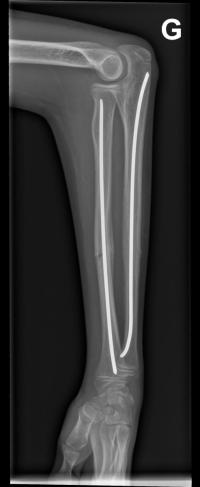

Fracture de l’avant-bras 31 mars 202519 mars 2024 par Damien Traitement Traitement orthopédique Embrochage centro-médullaire